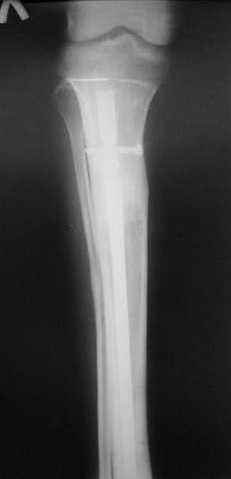

7, 8, 9, 10, 11 - через 8 мес после травмы перелом сросся.

Пациент ходит без дополнительной опоры, не хромает (видеоролик выложил сюда

http://rapidshare.com/files/14134274/Patient_B.AVI.html, вес 892 кб).